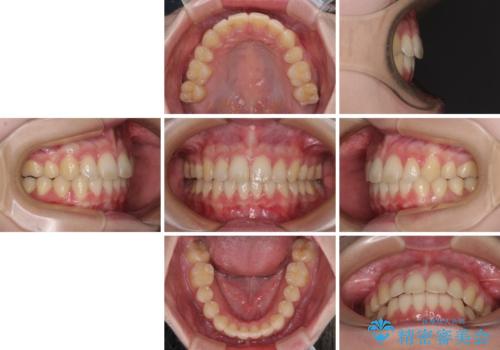

左側の咬み合わせと上下正中の位置をコントロールするために時間がかかりましたが、事前に思い描いた通りの歯列に整い、患者様には大変満足していただきました。